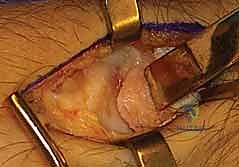

- الشق الجراحي: يُجري الدكتور هطيف شقاً جراحياً دقيقاً (حوالي 3-4 سم) على الجانب الكعبري للرسغ، متمركزاً فوق الحيز الظهري الأول (First Dorsal Compartment).

- حماية الأعصاب (الخطوة الأهم): يتم تحديد العصب الكعبري السطحي (Superficial Radial Nerve) وفروعه بدقة متناهية باستخدام تقنيات الجراحة الميكروسكوبية، وإبعاده برفق لحمايته من أي أذى. إصابة هذا العصب قد تؤدي إلى ألم مزمن أو خدر دائم.

- الوصول إلى المفصل: يتم فتح محفظة المفصل (Joint Capsule) لكشف الزائدة الإبرية الكعبرية والقطب البعيد للعظم الزورقي. يتم فحص مدى تآكل الغضاريف بالرؤية المباشرة.

- عملية الاستئصال (Osteotomy): باستخدام أزاميل دقيقة جداً (Osteotomes) أو مناشير جراحية صغيرة، يقوم الدكتور هطيف بإزالة الجزء المتآكل من الزائدة الإبرية.